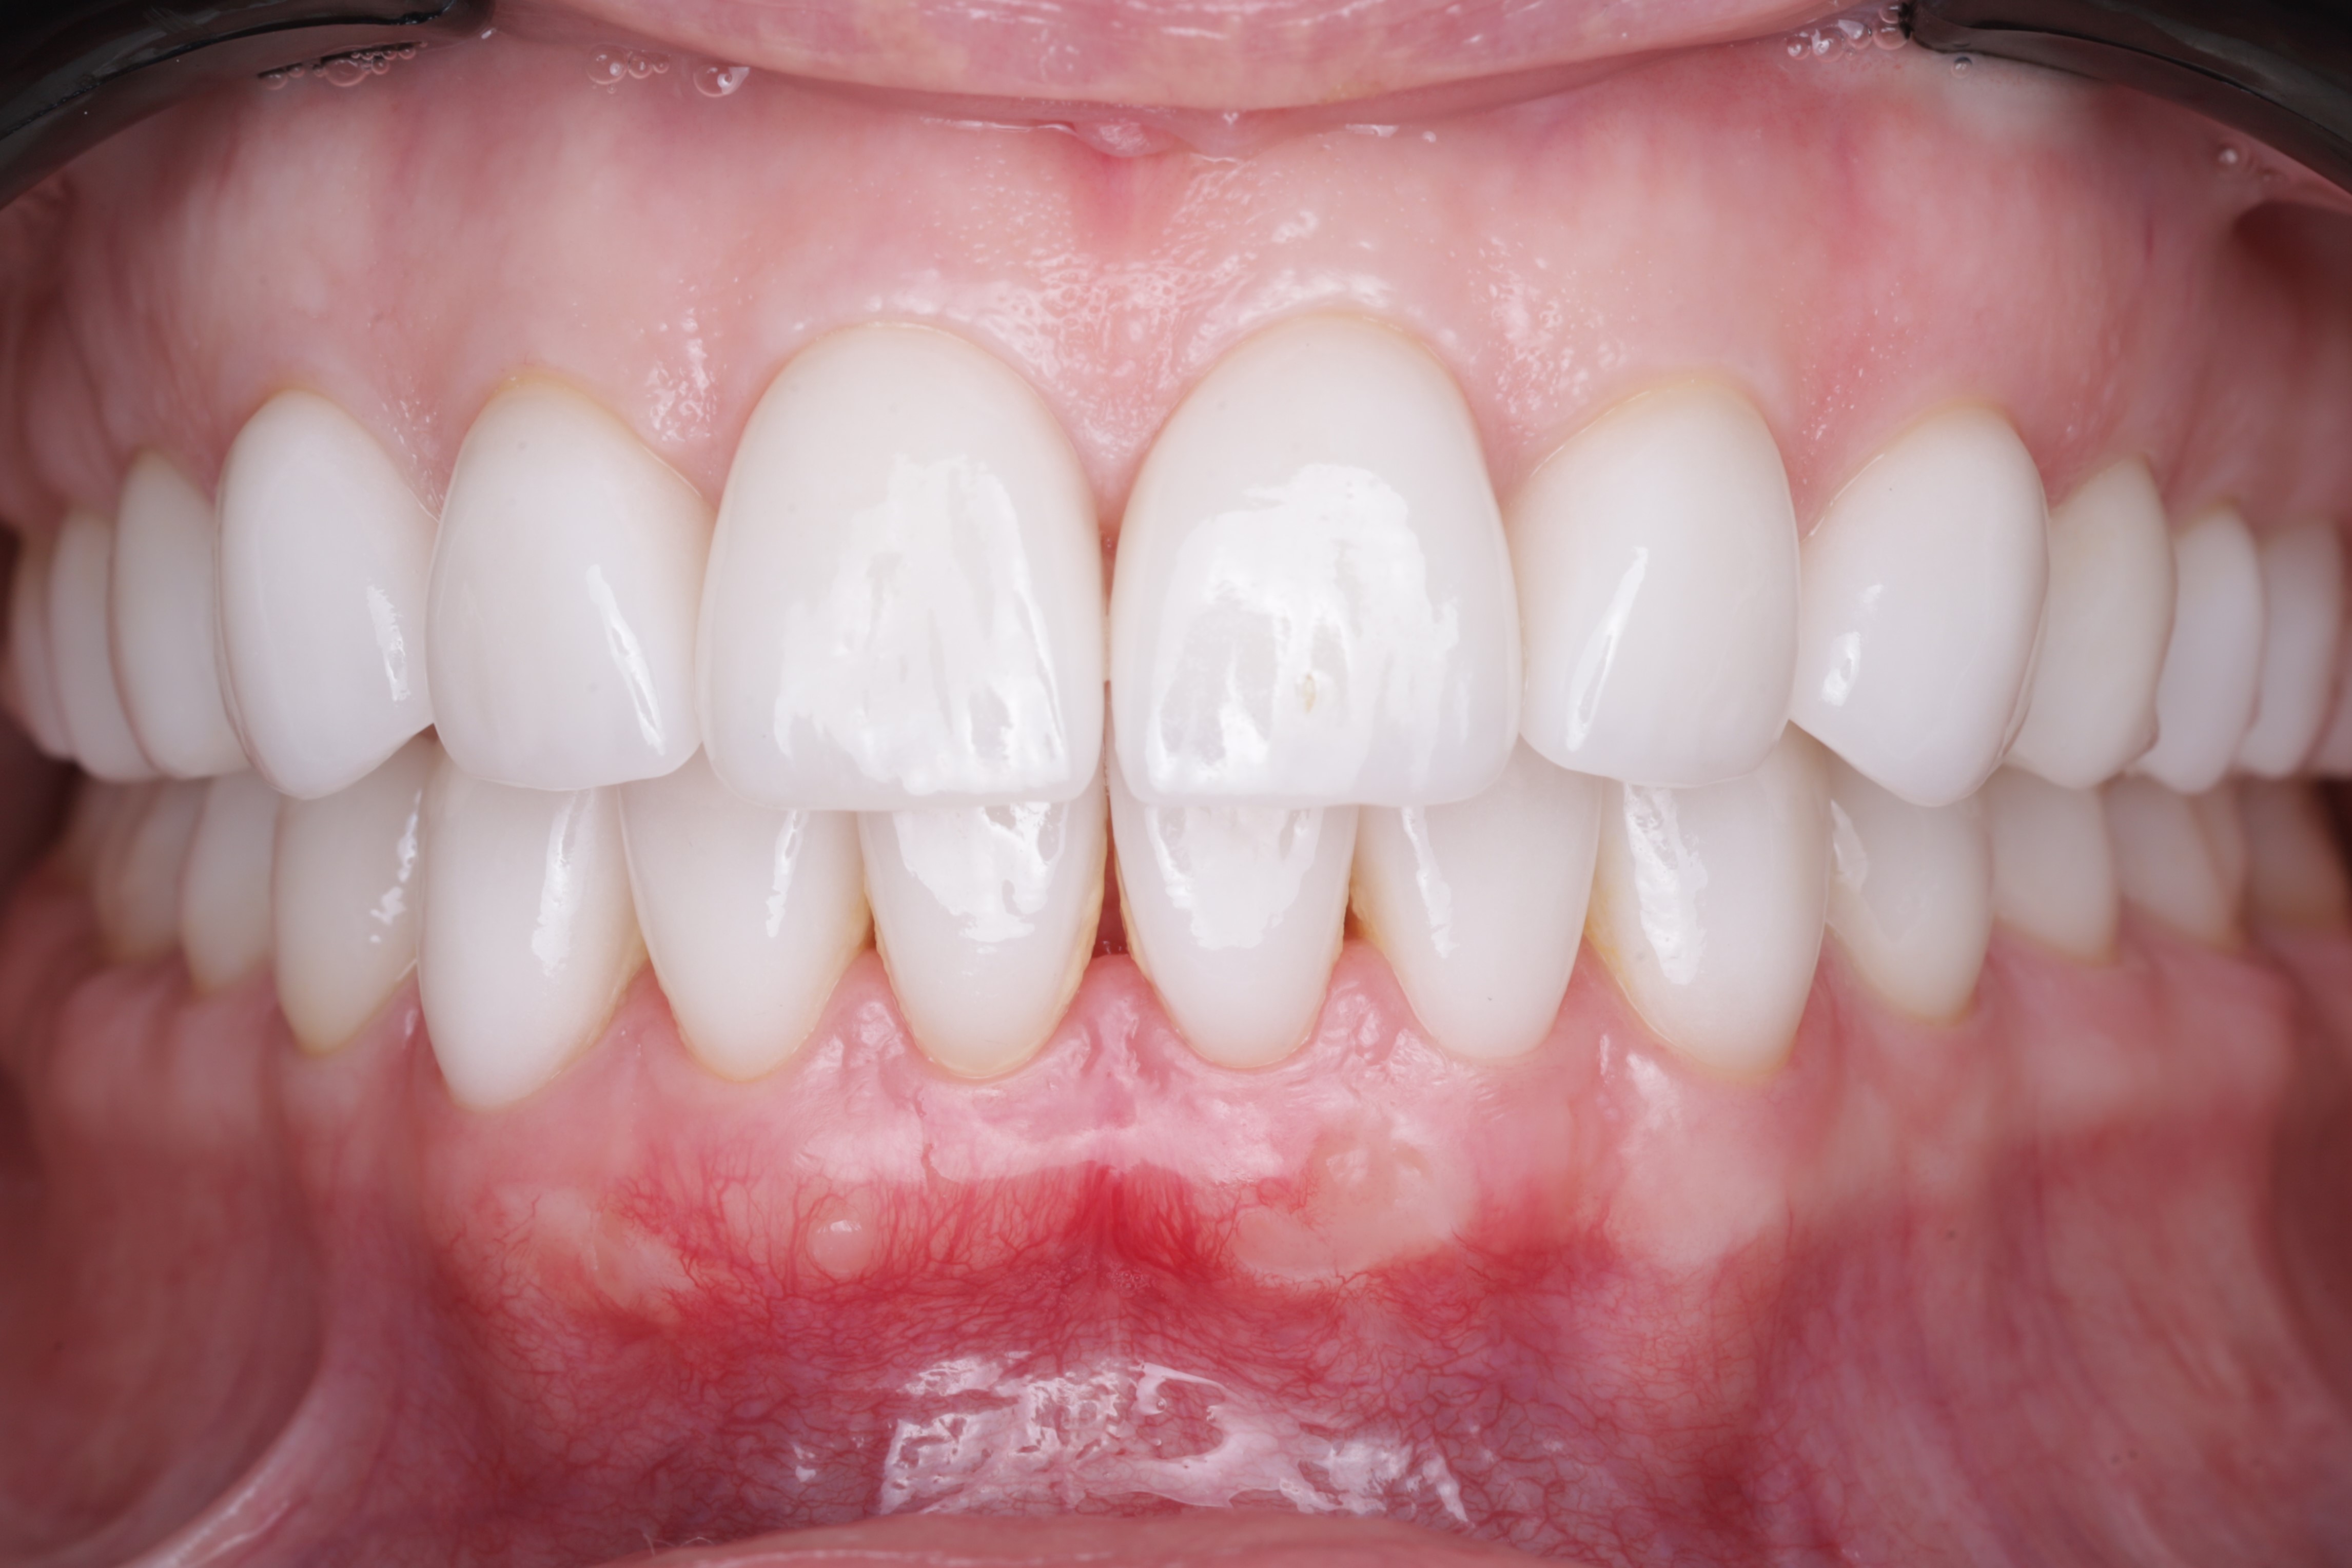

Через 3 недели после операции - видим немного гиперимированную слизистую и слегка  отечную в области проведенной операции